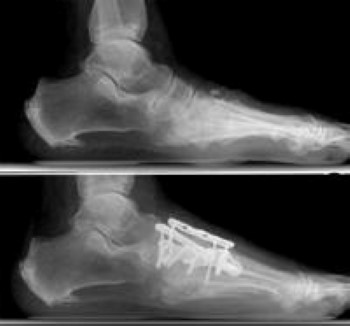

Arthritis Of The Foot And Ankle Orthoinfo Aaos